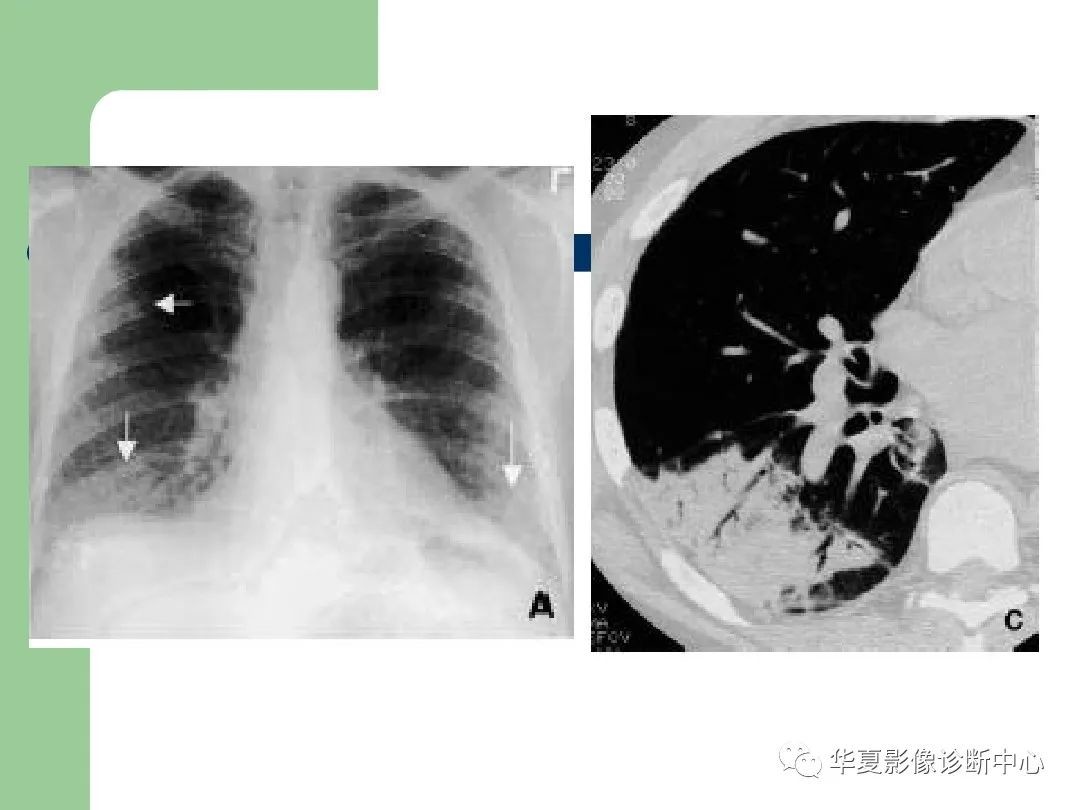

特发性间质性肺炎影像诊断